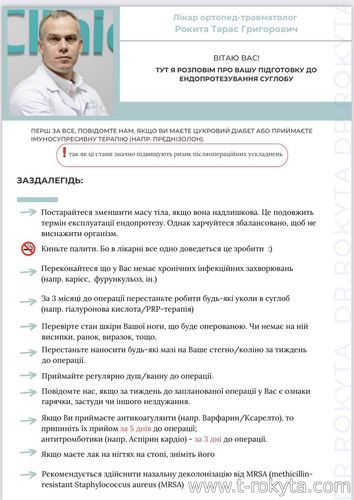

Виконуючи ендопротезування крупних суглобів часто чув від пацієнтів типові питання як до , так і в післяопераційному періоді. На основі цього постарався сформулювати основні тези-рекомендаціїї для пацієнтів ... Читати далі » |